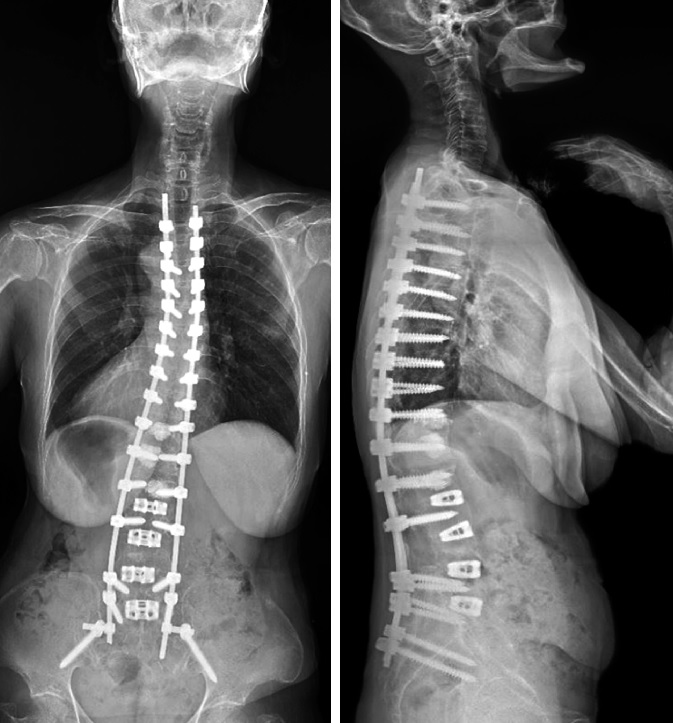

Proximal Junctional Kyphosis or forward curvature of the upper back (Kyphosis) is a common complication that develops in adult patients who undergo long posterior spinal surgery. This rate varies between 15% to 48%. However, several findings have shown that most cases occur within two years of spinal surgery, while two-third of the cases are reported within the first three months. PJK is known to be multifactorial in origin and is often diagnosed by radiography. The diagnosis of the PJK comprises a group of heterogeneous disorders, including acute pain, ambulatory difficulties, and in the most critical cases, neurological deficit. On the other hand, recent studies conclude Proximal Junctional Failure (PJF), the most progressive kyphosis, requires revised surgery for proximal extension of fusion.

As proximal junctional failure remains a challenging aspect of adult spinal deformity, several risk factors should be relatively considered before the surgery. PJK prevention strategies mainly focus on pre-operative planning, alignment, and steps to augment the upper-level fixation. These strategies can be applied, particularly in high-risk patients, to help reduce the rates of PJK.